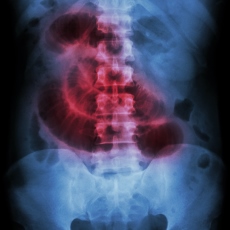

An intestinal obstruction occurs when food or stool cannot move through the intestines. The obstruction can be complete or partial. There are many causes. The most common are adhesions, hernias, cancers, and certain medicines.